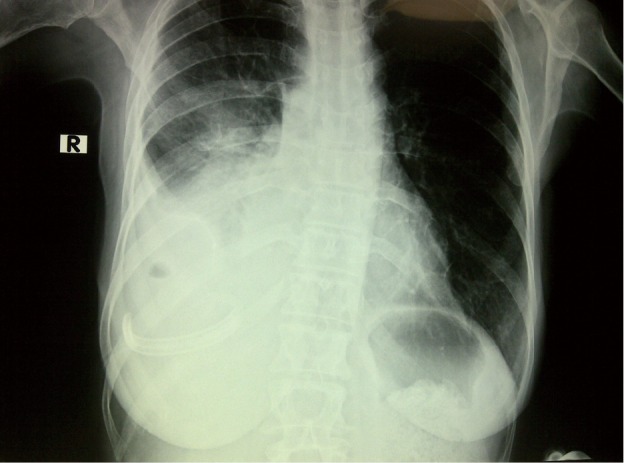

Figure 3.

Postoperative control radiograph of the Jackson Pratt (JP) drain.

The insertion sites for the prolonged pleural catheters (JP® Drain) were determined with thoracic ultrasound prior to the procedure in order to find a position for easy access. The catheters were inserted from the lateral chest wall in all patients. Prior to the procedure, complete blood counts, bleeding and coagulation times, a PTT, and PT measurements were carried out. When the insertion sites could be determined by posteroanterior chest X-rays or chest CTs the catheters were inserted directly, in the remaining patients, especially in the presence of loculated effusions the insertion site was marked with a thoracic USG (Figures 1,2). Mean procedure time for catheter insertion was 15-20 minutes. The location of the catheter inside the thoracic cavity was confirmed with a postoperative chest X-ray (Figure 3). Daily drainage was restricted to 1,500 mL to avoid lung edema, drainage was also stopped when an abnormal cough disturbing to the patient began. Ambulatory patients in good general condition were discharged either home or to the referring unit after receiving instructions on the use of catheters. The catheters were removed once drainage decreased to less 50 mL/day and lung expansion was achieved.